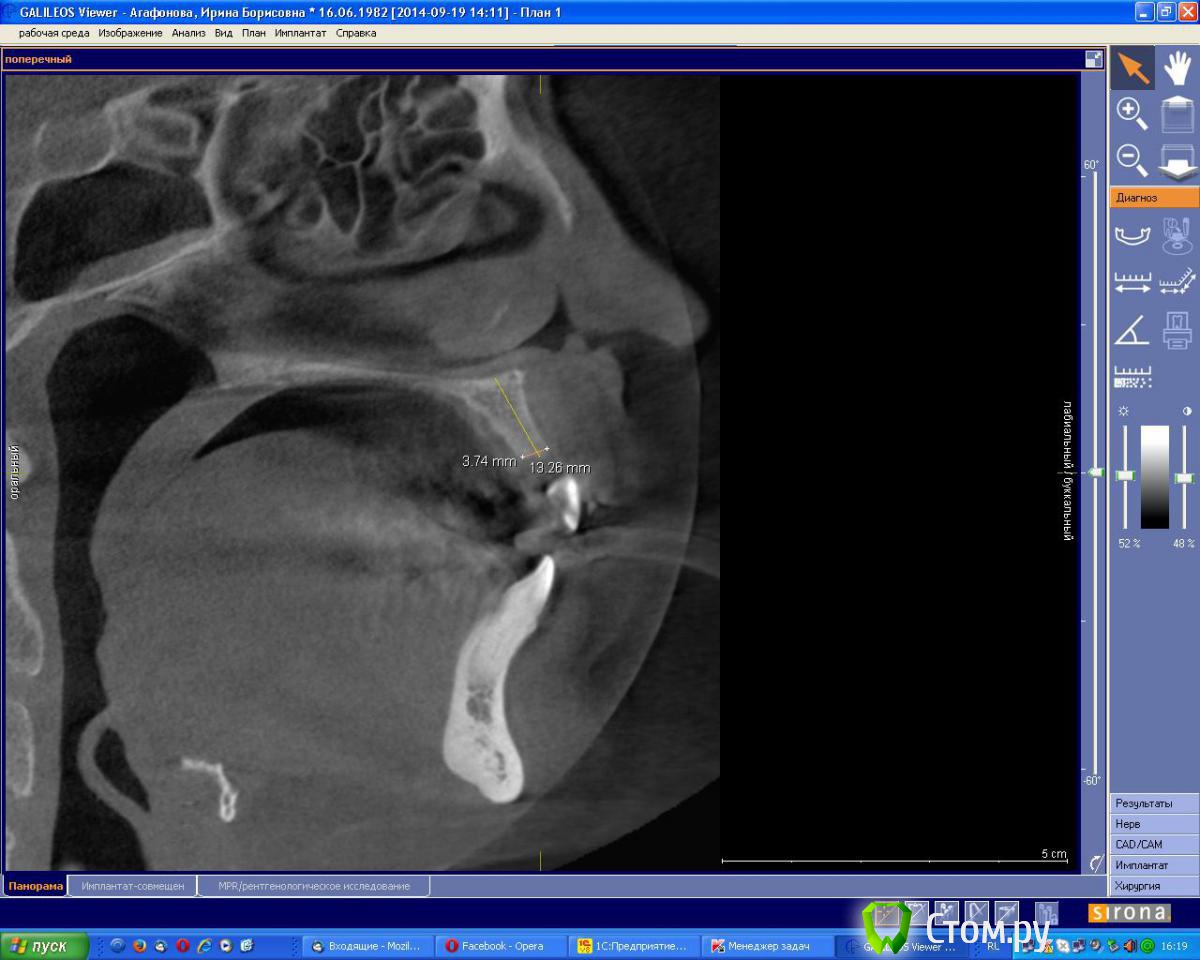

an_ver Опубликовано 19 сентября, 2014 Поделиться Опубликовано 19 сентября, 2014 (изменено) Молодая девушка,ранее был удален 21..с ее слов после удаления началось воспаление,выводили 2 месяца.После удаления-выведения прошло 6 месяцев. Сейчас фиксирован адгезивный мост. Вот такую картину имеем на сегодня. Что посоветуете,коллеги.Девушка хочет зуб Изменено 19 сентября, 2014 пользователем an_ver Ссылка на комментарий

an_ver Опубликовано 2 октября, 2014 Автор Поделиться Опубликовано 2 октября, 2014 Пики есть, уровень тоже. Согласен с Alexey Dok и faity, тут любая техника сработает от мембранной до ламината. Если эстетика немаловажна - VIP-CT или чего попроще.VIP на графт,сверху мембрану? Ссылка на комментарий